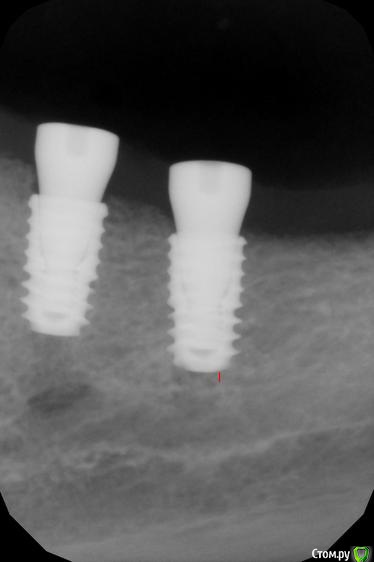

kamranchick Опубликовано 24 марта, 2016 Поделиться Опубликовано 24 марта, 2016 (изменено) Сегодня установливал имплантаты в 4 сегменте с фдмИ сделал снимки в 3 сегменте где ранее были установлены также имплантаты с фдмИмплантация была 5 Марта. Что это может быть?Торк 40 Изменено 24 марта, 2016 пользователем kamranchick Ссылка на комментарий

johniola Опубликовано 24 марта, 2016 Поделиться Опубликовано 24 марта, 2016 периимплантит 1 Ссылка на комментарий

kamranchick Опубликовано 24 марта, 2016 Автор Поделиться Опубликовано 24 марта, 2016 Есть варианты реабилитации на данный момент? Ссылка на комментарий

carloss Опубликовано 24 марта, 2016 Поделиться Опубликовано 24 марта, 2016 Есть варианты реабилитации на данный момент?вынимаем - ждем - ставим 1 Ссылка на комментарий

Аслан Опубликовано 25 марта, 2016 Поделиться Опубликовано 25 марта, 2016 была у меня недавно похожая ситуация. поставил в зону 46 8 мм и в зону 47 7 мм диаметром 4 мм под заглушки.паца жаловалась на боль пару месяцев. приехала на фдм, выкрутил 47, слегка прошелся фрезой 5мм диаметр , отшкрябал и врутил сразу с фдм 7х5мм, полет нормальный. не стал бы такое за практику брать, просто паца приезжая. Ссылка на комментарий

kamranchick Опубликовано 25 марта, 2016 Автор Поделиться Опубликовано 25 марта, 2016 Просто если выкручивать, и через 2 месяца вкручивать боюсь ничего от косточки не останется( а расширять ложе там места нету уже. кт выложу)) Ссылка на комментарий